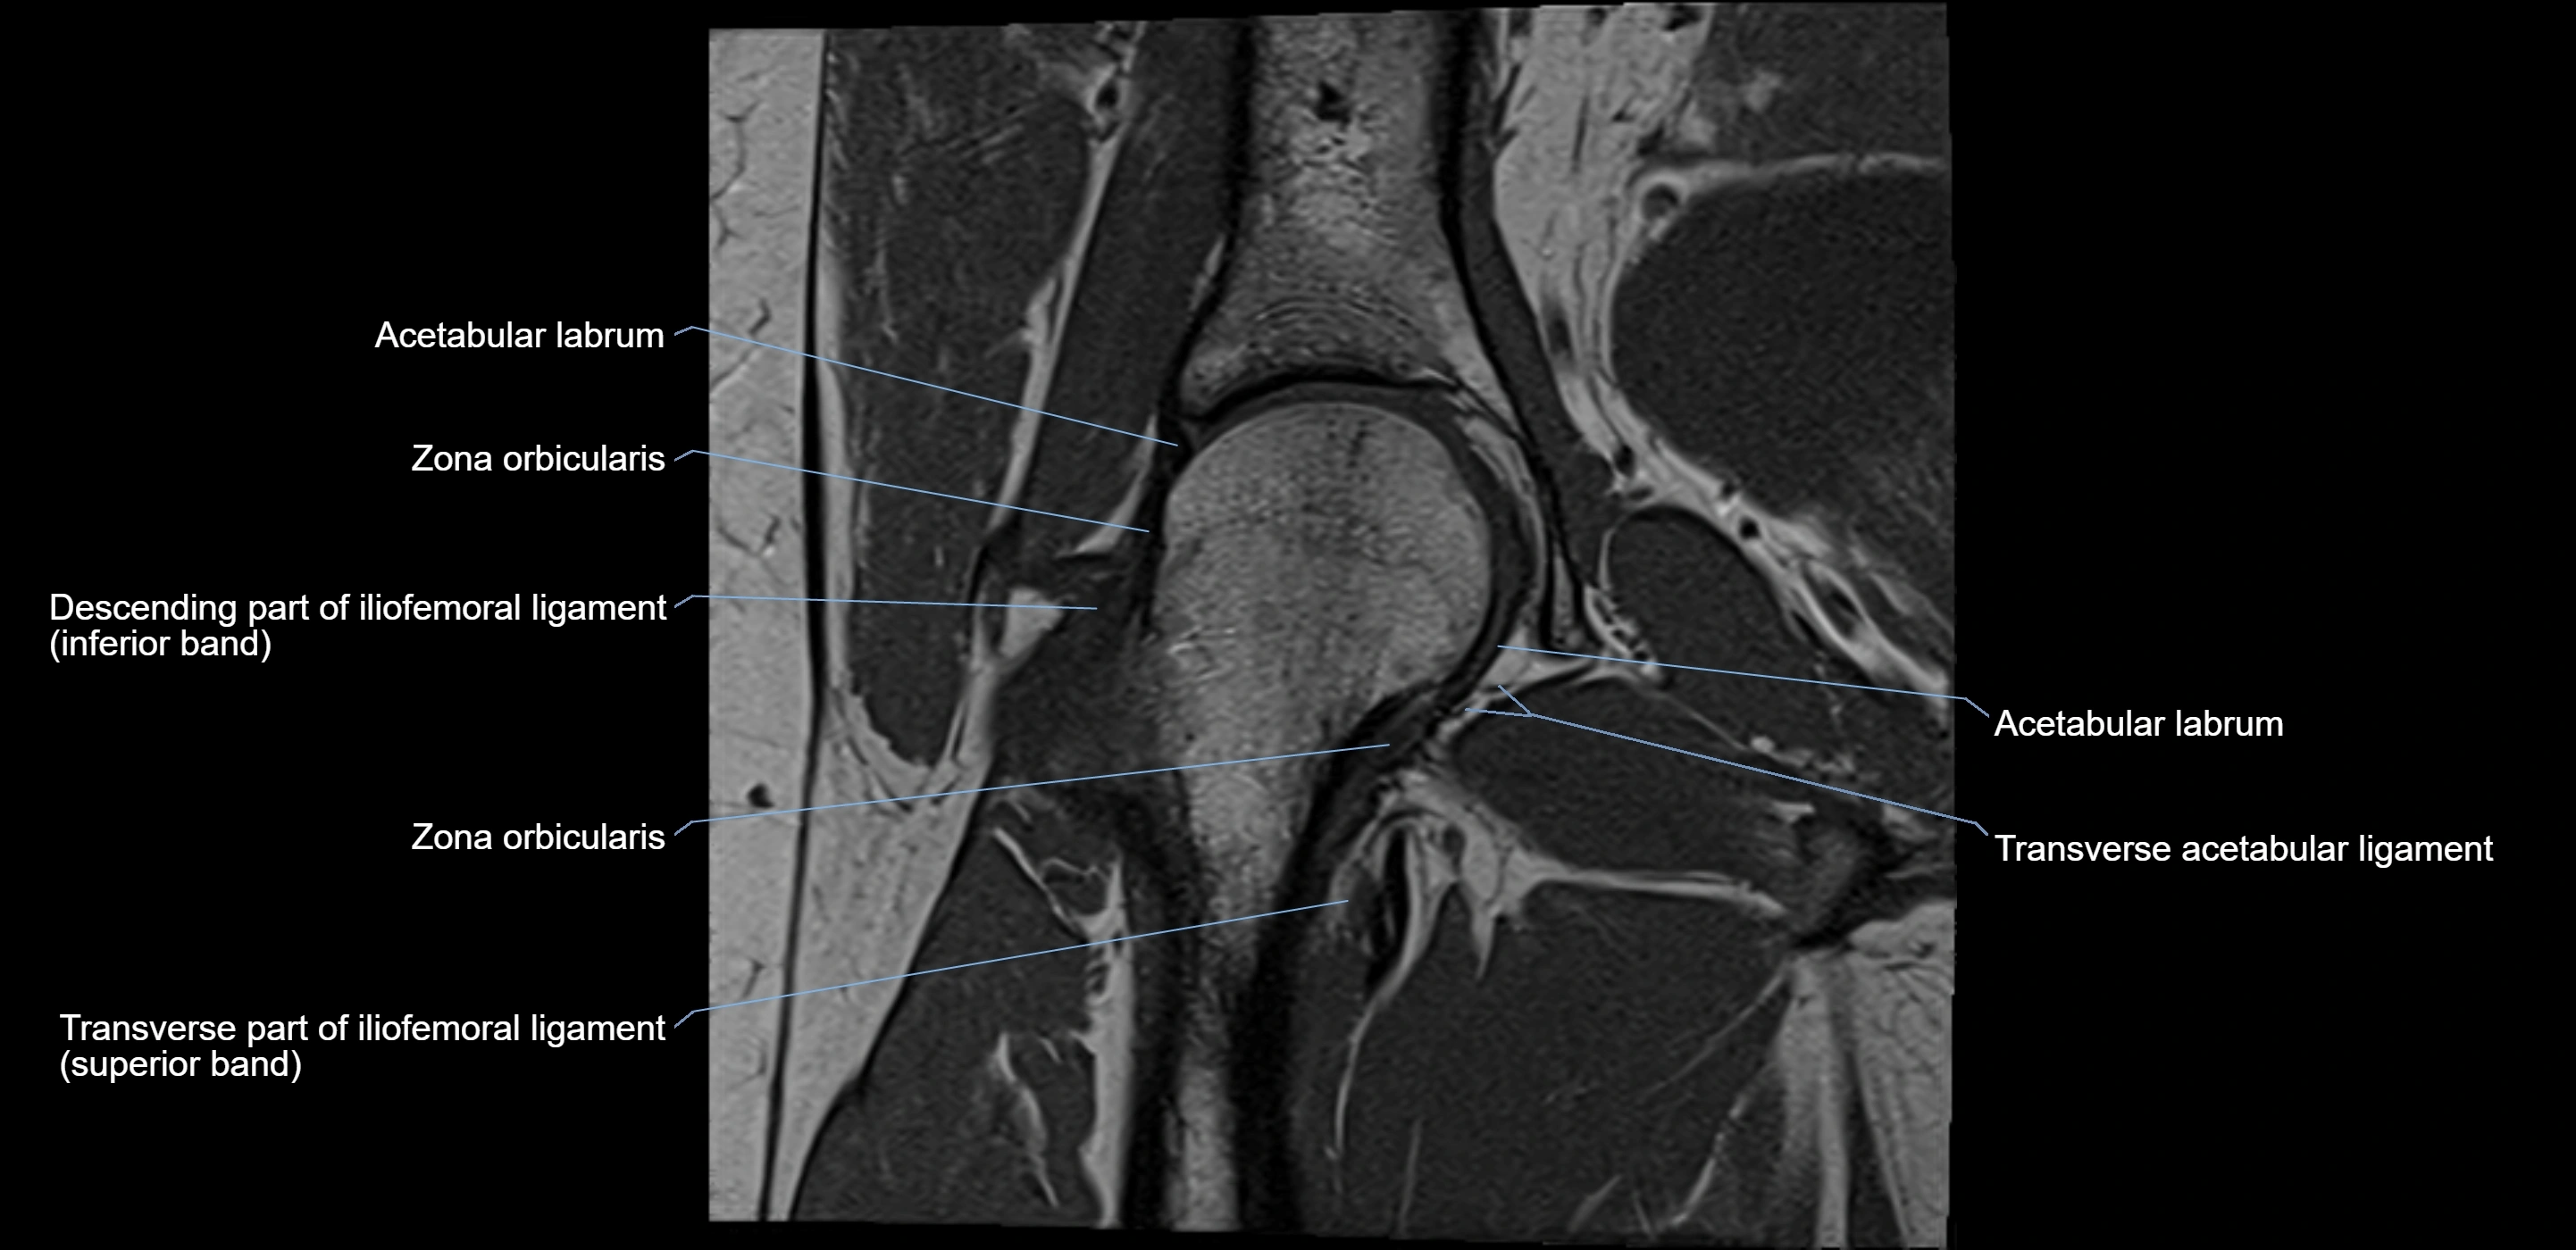

The acetabular labrum is a fibrocartilaginous ring that surrounds the rim of the acetabulum in the hip joint. It deepens the hip socket, increases joint stability, and maintains a suction seal that preserves negative intra-articular pressure. Structurally, the labrum transitions from hyaline cartilage of the acetabulum to dense fibrocartilage at its free edge.

It is triangular in cross-section, with its base attached to the acetabular rim and its apex projecting toward the femoral head. The labrum is most robust superiorly and anteriorly, where load bearing is greatest, and relatively thinner inferiorly.

Structure and Relations

• Superior and anterior labrum: thickest portions, stabilizing against anterior dislocation

• Inferior labrum: blends with the transverse acetabular ligament bridging the acetabular notch

MRI Appearance

T1-weighted images:

• Labrum: low signal intensity (dark)

• Surrounded by intermediate signal joint fluid (bright on arthrogram)

• Tears: linear or focal areas of intermediate-to-high signal interrupting labral continuity

T2-weighted images:

• Joint fluid: bright, making labral tears visible as fluid extending into or around labrum

• Degeneration: may show areas of increased signal within labrum